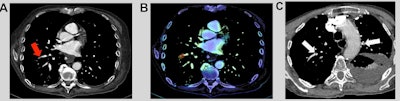

Clinical examples. A 71-year-old patient with a medical history of cancer and recent surgery presented with heart rate > 95 beats per minute and a borderline saturation and underwent a CTPA. The CTPA showed a segmental, sub-acute, PE in the right low limb, which was missed by the emergency radiologist during his on-call duty (red arrow). B: On the same cross-section, the PE was correctly identified by the AI algorithm (AIDOC Medical). Example of PE was correctly diagnosed by the emergency radiologist and not by the AI algorithm. Opposite example: An 85-year-old patient with a medical history of PE and a recent surgery presented with a heart rate between 75 and 94 beats per minute and acute dyspnea and underwent CTPA (C). Two segmental PEs were correctly diagnosed by the emergency radiologist but missed by the AI algorithm (white arrows).

Clinical examples. A 71-year-old patient with a medical history of cancer and recent surgery presented with heart rate > 95 beats per minute and a borderline saturation and underwent a CTPA. The CTPA showed a segmental, sub-acute, PE in the right low limb, which was missed by the emergency radiologist during his on-call duty (red arrow). B: On the same cross-section, the PE was correctly identified by the AI algorithm (AIDOC Medical). Example of PE was correctly diagnosed by the emergency radiologist and not by the AI algorithm. Opposite example: An 85-year-old patient with a medical history of PE and a recent surgery presented with a heart rate between 75 and 94 beats per minute and acute dyspnea and underwent CTPA (C). Two segmental PEs were correctly diagnosed by the emergency radiologist but missed by the AI algorithm (white arrows).In addition to confirming the high diagnostic performance of AI algorithms for diagnosing PE on CTPA exams, the study demonstrated how AI can best support radiologists, according to the researchers. The algorithm showed particular value in poor-quality examinations and by increasing diagnostic confidence via its high sensitivity and negative predictive value.